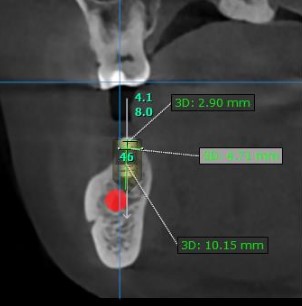

Good morning everyone, I would like to get your opinion on the following treatment options for this case. This patient has missing 47, 46 and a retained root at 45. Interocclusal space is about 5mm ( so i cannot perform vertical bone augmentation), bone height is limited, about 10mm ( close proximity to ID canal) and bone width is not satisfactory as well . I have not used any short implants with high engaging threads ( BLX implant) in my practice so I would like to get everyone’s input on this. Thank you.

Treatment plan 3 units straumann BLT implant (45 : 4.1mm x 8mm, 46 : 4.1mmx8mm, 47: 4.8mmx8mm) + GBR with autogenous and straumann xenograft + 2 units splinted 46,47 and single unit 45 final prosthesis

– Concern – Longer implants but near to ID canal, about 1-2mm away if place implants at the same level at bone crest and limited/abscence of buccal bone